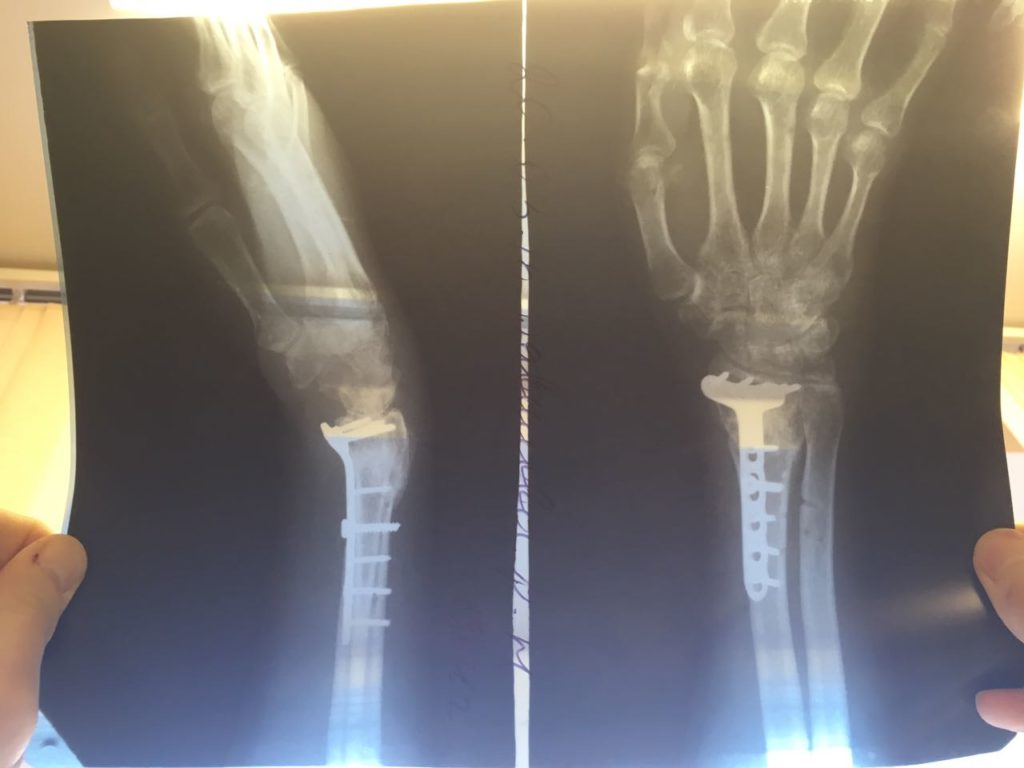

Операция - открытая репозиция, остеосинтез лучевой кости пластиной с костной ксенопластикой материалом "Остеоматрикс". На контрольных снимках в три месяца имеется консолидация перелома, миграции фиксатора нет, имеется остеоинтеграция ксенопластического материала.

Отдаленные результаты через 6 (шесть) месяцев